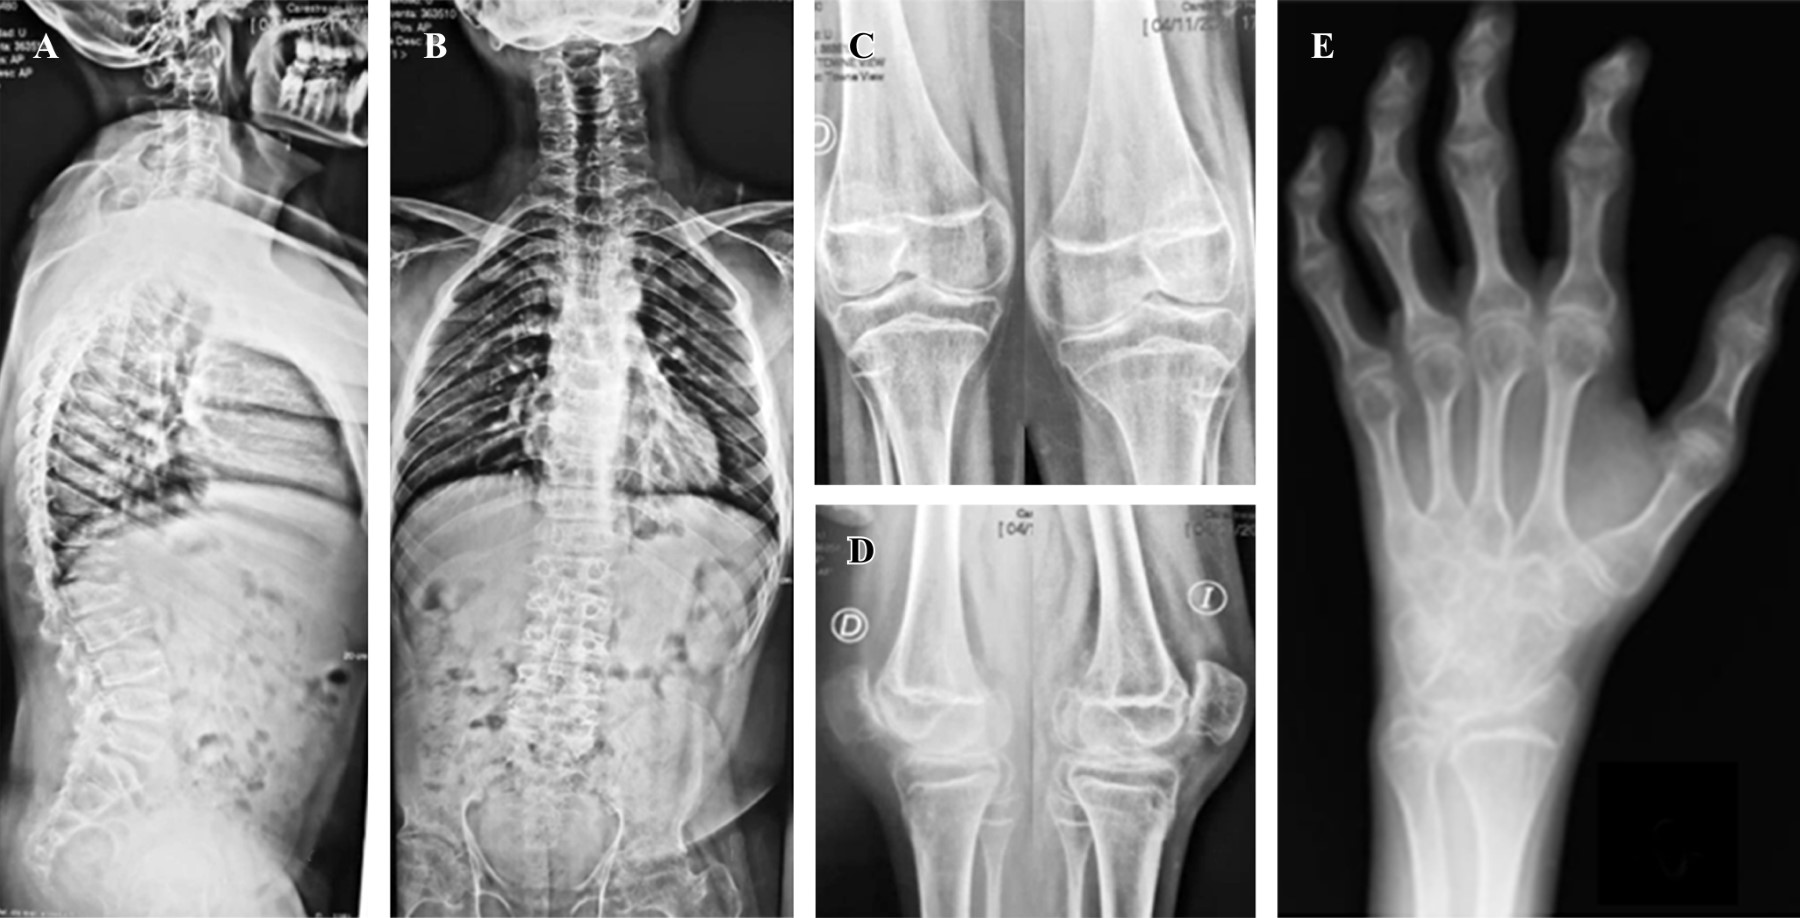

Progressive pseudorheumatoid dysplasia (PPD) is an autosomal recessive hereditary disease of very low prevalence. It is characterized by the affection of multiple joints, generating arthrosis and progressive deformities from a very young age, which significantly affect the quality of life of patients. Its diagnosis is only confirmed by genetic testing, and no specific pharmacological treatment is still available. In the case of hip involvement, one treatment option is arthroplasty. In this case report, we present a 15-year-old boy with bilateral coxarthrosis secondary to PPD who underwent bilateral total hip arthroplasty in two stages. We highlight the characteristics of this rare entity, the intraoperative findings, the functional outcomes, and the impact on quality of life.

Figure 3